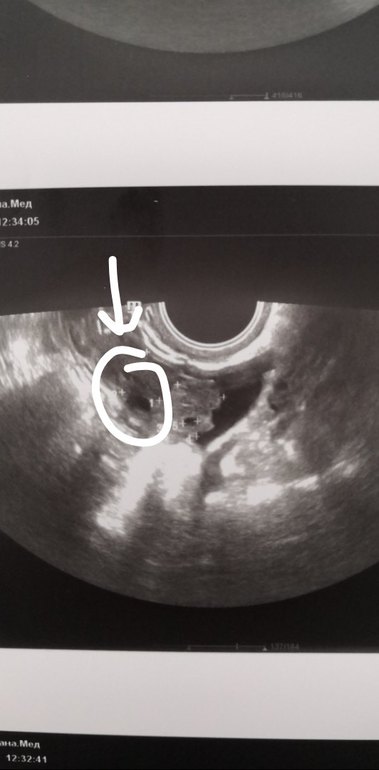

Анализы, скринингиДевочки! Скажите пожалуйста, 1Б, ХГЧ 718, анализы в норме? Мы ещё совсем маленькие, 2-3 недели. Просто врач вчера напугала, что беременность возможна внематочная. Очень переживаю!

УЗИ вагинальное? Что-то я не пойму - там несколько участков затемнённых....